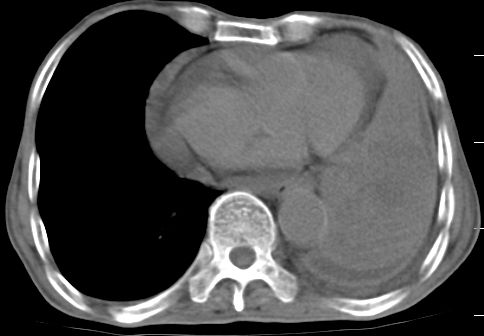

标题: CT10141:男、84岁,咳嗽、咯血1年。 [打印本页]

标题: CT10141:男、84岁,咳嗽、咯血1年。

1左侧胸腔积液并包裹2心包积液3左下肺癌?建议支纤镜检。

支持左侧中央型肺癌伴下叶肺不张\\纵隔淋巴结转移.左侧包裹性胸腔积液\\心包积液.左侧少量胸腔积液..慢性支气管炎伴部分间质纤维化.

咯血病史较长,左肺下叶实变,体积未明显缩小,隐约可见血管影及坏死阴影,双肺门及纵隔淋巴结增大,心包增厚积液,纵隔右移位,单侧胸腔积液,首先考虑:大叶型肺泡癌伴纵隔心包转移。